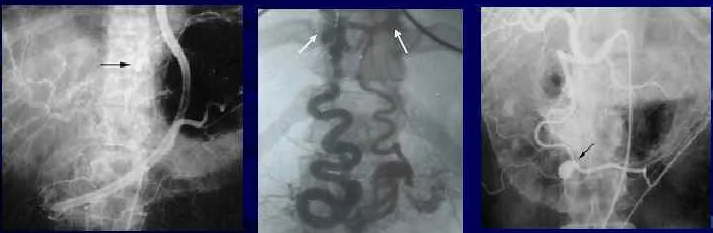

нахождения в стационаре. Для уточнения диагноза и лечения инвагинации

кишечника у 57 детей применяли пневмоирригоскопию открытым методом без

обтуратора. На первом этапе диагностируется наличие инвагината, а

дальнейшее нагнетание воздуха способствует расправлению его.

Положительные результаты получены у 17 больных. Критерием дезинвагинации

является заполнение воздухом всего толстого кишечника и проникновение

его в тонкую кишку. После дезинвагинации изученный ребенок обычно

засыпает ещё в рентген- кабинете, пальпируемое опухолевидное образование

живота исчезает, а через 2-3 часа у него появляется стул.